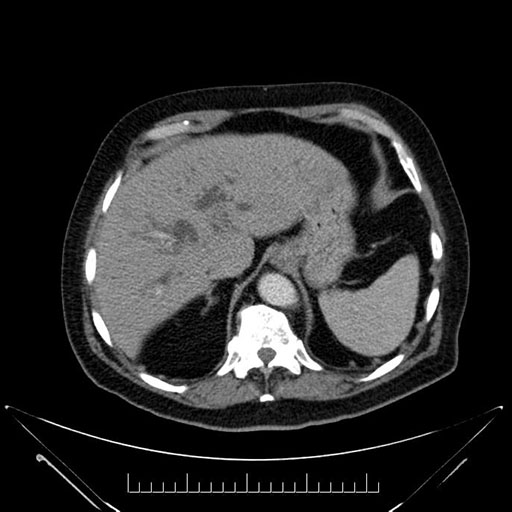

Whipple (pancreaticoduodenectomy) [case 7]

Imaging Analysis

Look through the patient's CT scan to identify any areas of concern for the necessary procedure.

Based on your CT findings, which issue(s) would give reason for "planned slowing down moment(s)" in this case?

Considering a standard Whipple procedure, what step(s) of the operation would you do differently in this case?